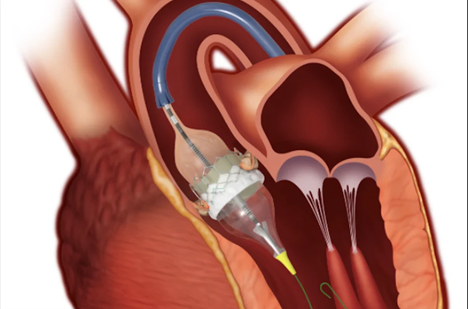

Implante transcateter de válvula aórtica (TAVI)

O implante transcateter de válvula aórtica visa substituir a válvula aórtica doente, uma doença que geralmente acomete indivíduos de mais idade. Antigamente, essa doença somente poderia ser tratada através de uma cirurgia cardíaca convencional, porém hoje esse tratamento é possível através de uma pequena incisão na virilha e tem se tornado o tratamento de escolha para a maioria dos pacientes com mais de 70 anos. Esta técnica este relacionada a altas taxas de sucesso e baixas taxas de complicações. O time do Hospital INC é referência neste procedimento, utilizando técnicas, materiais e equipamentos de última geração

Representação de um implante transcateter de válvula aórtica.